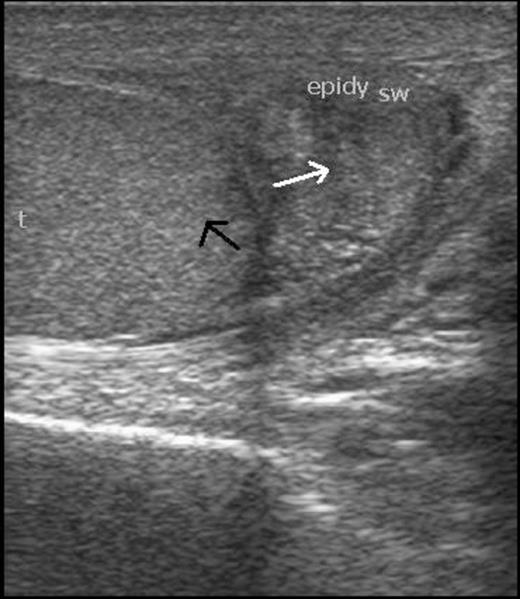

A 24 year old male presented with progressively increasing painless swelling of the right epididymis for 2 months. There was no history of trauma. His past and personal history was not significant. Local examination revealed a firm, mobile, mildly tender mass measuring 1.5x1.5cm in diameter in the right epididymis. Testes were normal bilaterally. Clinically, a diagnosis of epididymal cyst was made. Routine hematological and biochemical tests were within normal limits. Ultrasonography of the swelling revealed a well-defined hypoechoic lesion of 18x11mm, with increased flow on color Doppler (Figure 1).

Scrotal ultrasonography. Well defined hypoechoic lesion of size 18x11mm in right epididymis (white arrow) and normal right testis (black arrow)